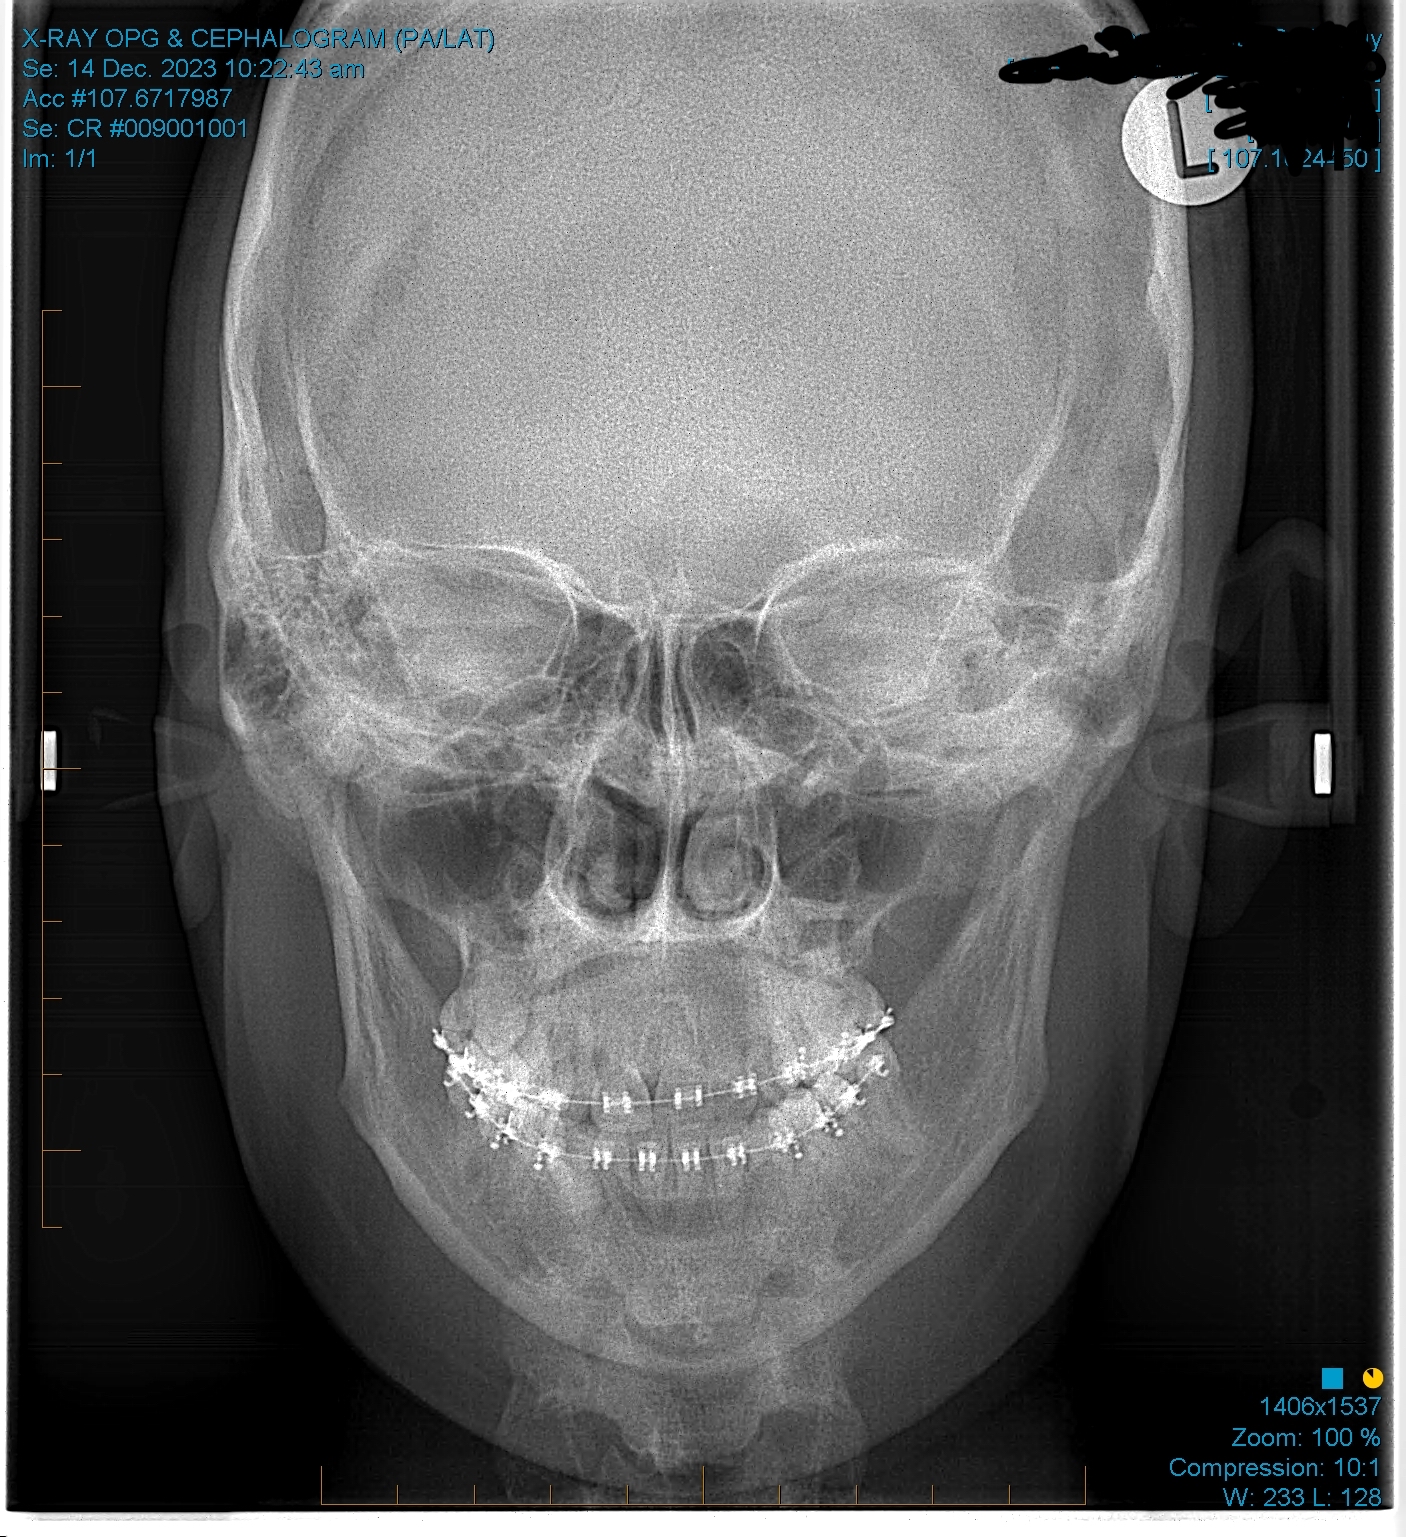

sfs, no ramus and zygos, retrusive, low hyoid, crossbite, crooked/slanted and retracted maxilla, mandible asymmetry, right side of face grown more than left, 8 extractions at 13 (including premolars).